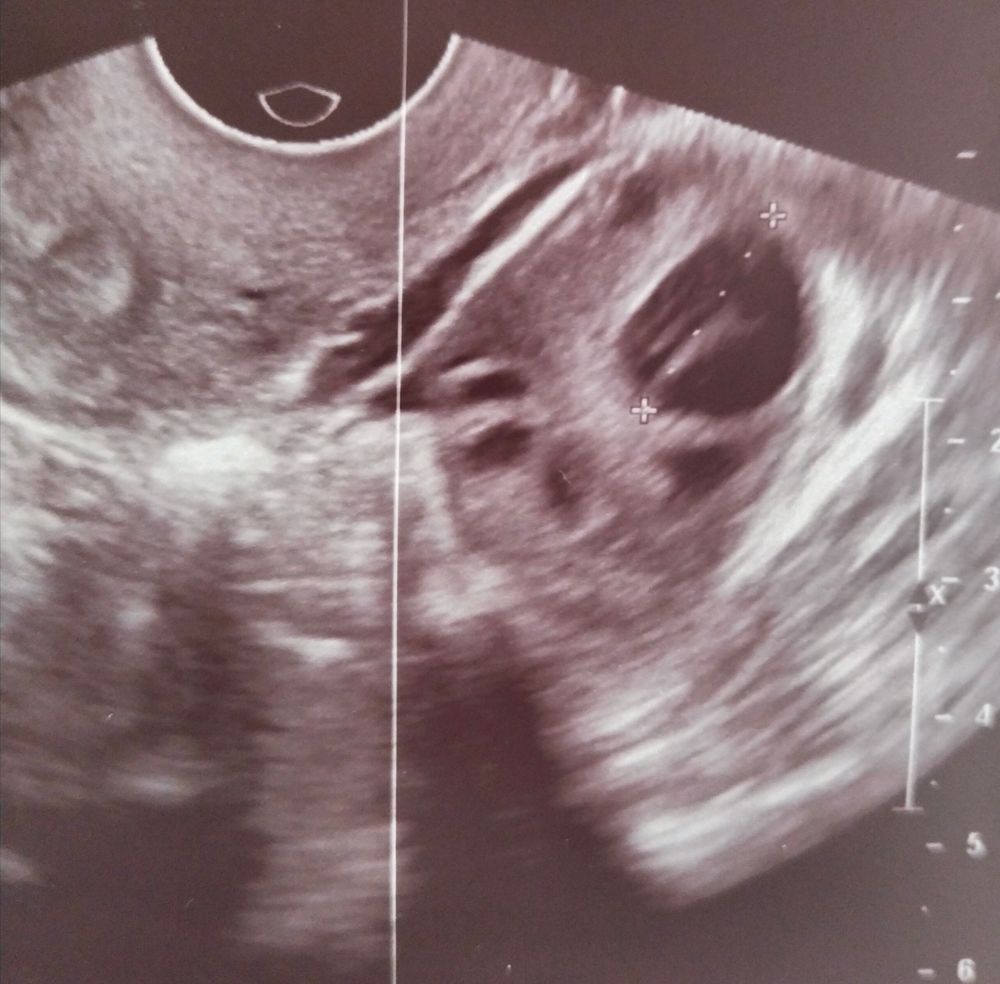

Зайдите в мой пост, у меня поставили доминантный фолликул с похожими штрихами. Можно ваше фото без маркера ?

Александра , а вот мой доминантный фолликул. Мне сказали - овуляции не было и не будет. Как по мне, у меня даже больше этих штрихов внутри.